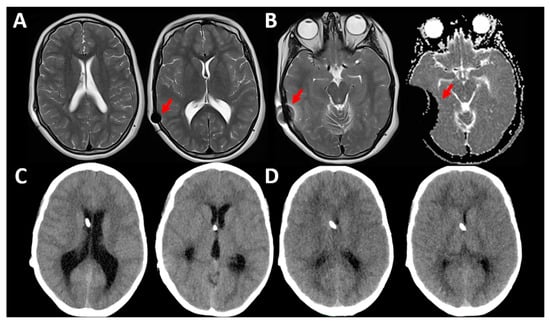

Figure 8.

This 13-year-old girl had surgery for a Chiari 1 malformation with hydrocephalus. She had a Hakim programmable valve implanted with an OP of 70 mmH2O. The patient was scanned in a 1.5 T MRI for control (A,B). In (A), the ventricular size was normal. Arrows show the magnetic artifact produced in the different MR1 sequences that was moderate in T2-weighted images and very strong in the diffusion-weighted sequences (B). The patient’s valve was accidentally reprogrammed by the doctor on call to an OP of 150 mmH2O immediately after the MRI. She was admitted three days later because of headache and drowsiness. The CT scan on admission (C) showed a significant increase in the ventricular size. The OP of the valve was readjusted to 70 mmH2O. The patient improved and the new CT scan at discharge is shown in (D).